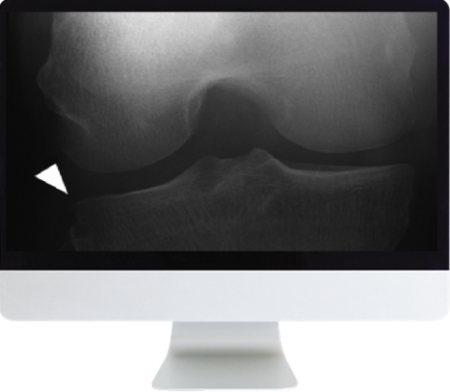

Ligamentous Inguries of the Knee: Analysis of MRI Footprints—D. Resnick

Meniscal Lesions in the Knee: Basics and Beyond—C. Chung